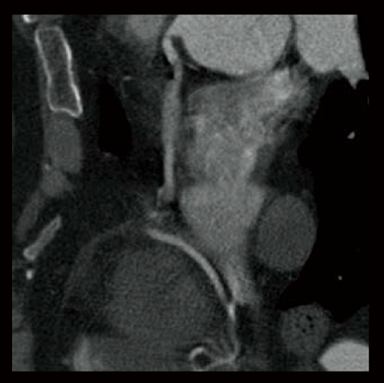

Dans les examens TDM cardiaques, les différents facteurs tels que la fréquence cardiaque et les mouvements du cœur affectent la qualité de l’image. Avec les méthodes conventionnelles de reconstruction d’image, des artères coronaires non focalisées et des artefacts causés par le mouvement peuvent apparaître, ce qui se traduit par des images ne répondant pas à la qualité attendue, ce qui peut affecter le diagnostic. Pour résoudre ces problèmes, Fujifilm a développé Cardio StillShot, qui calcule la direction et la quantité de mouvement du sujet en quatre dimensions à partir des données brutes collectées pendant les examens TDM cardiaques, et les corrige pendant la reconstruction de l’image pour obtenir une résolution temporelle effective de 28 msec.*1 La résolution temporelle effective contribue à améliorer la capacité de diagnostic en fournissant des images cliniques focalisées de haute définition avec moins d’artefacts de mouvement, même chez les patients ayant une fréquence cardiaque élevée.

Cardio StillShot : OFF

ON